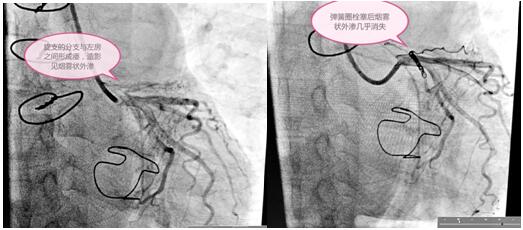

定于3月3日進行冠狀動脈瘺彈簧圈栓塞手術(shù),術(shù)前手術(shù)團隊為患者細心指導(dǎo),消除患者緊張情緒,穿著手術(shù)衣,帶著一次性手術(shù)帽和普通外科口罩,做好防護。吳棟梁院長和高勝利主任手術(shù)團隊為患者精心進行了手術(shù),要將大小合適的彈簧圈放在血管遠端狹窄處封住瘺口,患者冠脈及分支血管比較迂曲,會導(dǎo)致手術(shù)過程比較復(fù)雜,耗時長,這些在手術(shù)方案里均考慮到。初始常規(guī)使用的導(dǎo)絲通過困難,后來根據(jù)患者血管走形我們又選擇了微導(dǎo)管和特殊的導(dǎo)絲,導(dǎo)管室很安靜,能聽到的只有時鐘的滴答聲和我的心跳聲,調(diào)整了手術(shù)器械后彈簧圈很快送到位并釋放,手術(shù)終于圓滿結(jié)束,比我們預(yù)計的手術(shù)時間提前了半小時。

術(shù)前與術(shù)后